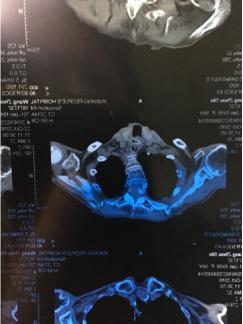

10月24日上午,一名98岁患者因勿吞枣核来我院消化内科就诊,患者于10月22日在当地做过CT检查,报告显示食管上段平声门下水平可见一横行管状高密度,边缘可见结节状略高密度,周围软组织肿胀,家属告知此患者心功能不全病伴心衰、房颤病史,在当地医院就诊因患者异物位置高,内镜下取出难度大,且患者高龄伴有严重原发病,推荐患者到我院就诊。10月24日上午患者转诊至我院,消化内科主任刘吉勇亲自为患者做内镜下异物取出术,在杨崇美主任医师、刘华琳护士长及医护团队配合下,给患者吸氧、心电监护前提下,经过约15分钟时间成功将患者食管上口的枣核取出。